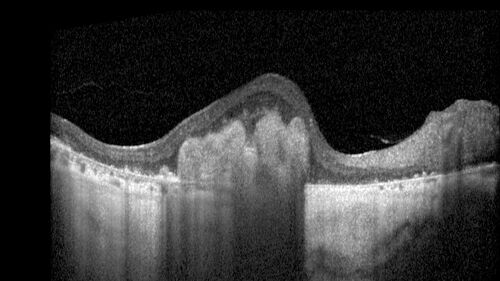

BRAO - plaques in vessels - GIF video of FA

78 year old female with vision loss for 1 week and old macular scar. Images show BRAO with plaques and FA shows occlusion.